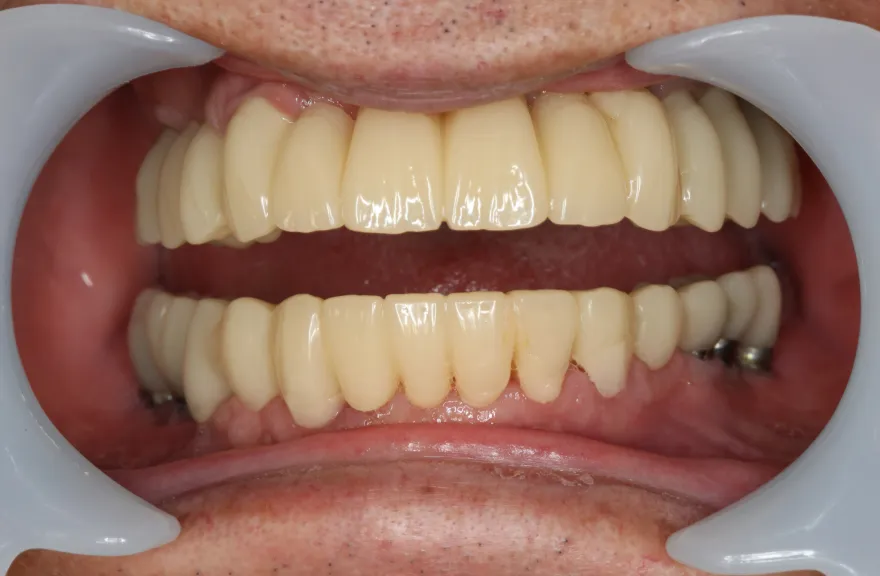

年齢を考えると、今回の治療で歯科治療を終えてしまい、残りの人生においてはメンテナンスのみで歯科へ通う状況を作りきってしまうことが求められました。

以上より、潔く残っている歯牙は抜去させていただき、上下をインプラントフィクスチャーによって固定式の歯を入れることとしました。 - 治療のリスク

複数のインプラントフィクスチャーの埋入においては埋入位置がずれると後々のクラウン製作に難が生じます。そのリスクを最低限にするため、ガイデッドサージェリーを行っております。